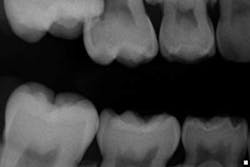

Case report A healthy 7-year-old female presents for a routine examination and cleaning (she had not been seen for two years). Crowding was noted primarily in the mandibular arch; the maxilla had a high palate. A significant amount of plaque/debris was noted in the upper right area between partially erupted No. 3 and tooth A. A bitewing radiograph on the right side barely revealed an ectopic eruption of tooth No. 3. (Fig. 1)Fig. 1Periapical and panoramic radiographs were taken and exposed a 50% resorption of the distal root and pulp chamber of tooth A. (Figs. 2 and 3)

Fig. 2